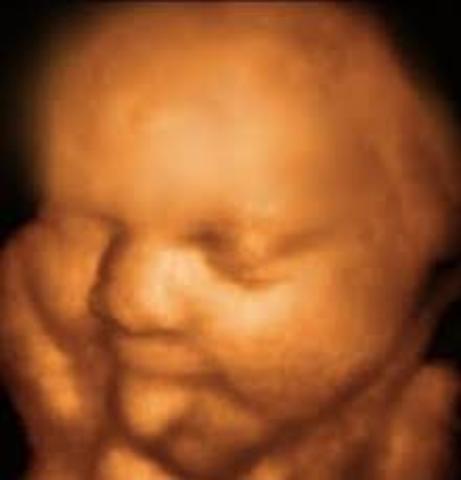

• Semana decimo segunda de gestación

Semana decimo segunda de gestación

El niño mide unos 6 centímetros y su peso oscila entre los 8 y los 14 gramos. La mayor parte de las estructuras internas ya están formadas y, a partir de ahora, seguirán perfeccionándose y creciendo. El aparato genital externo del bebé empieza a definirse, aunque con los ultrasonidos de la ecografíaaún no es posible distinguir el sexo del feto. Con esta semana, termina el período de "embriogénesis", durante el cual el embrión está más expuesto a los peligros que podrían perjudicar la correcta fo